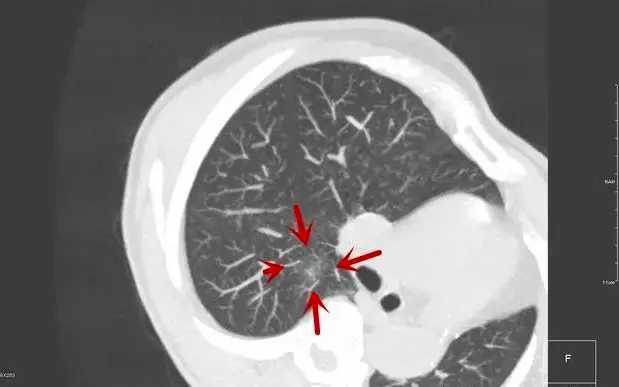

把人体的肺看成是一颗倒着的树

不同术式的示意:我们可以将人体的肺看成是一颗倒着的树,气管就是树干,它往上分2支,分别是左主支气管与右主支气管;再往远端,右侧分3支,分别为上叶、中叶、下叶;左侧分2支,分别为上叶与下叶;如果肺叶支气管再往远端分,就是肺段支气管。肺叶切除就是切除上述两侧5叶中的一叶,肺段切除就是切除某一肺叶中再往下一级的结构,全肺切除就是切除全部左边的肺或者全部右边的肺;袖式肺叶切除就是将肺叶以及叶支气管开口对过去的主支气管壁也切掉,再将余下的肺叶支气管与主支气接起来。